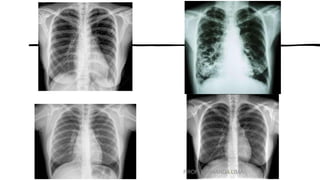

• •Identificar e contar os pares

de costelas.

• (O 1º e 2º pares são os mais

difíceis de localizar.)

• Observar o grau de

deslocamento

do diafragma para baixo

através da contagem dos

pares de costelas

projetadas acima

das cúpulas do

diafragma.

• Uma regra geral para a

média dos adultos

é “mostrar” um mínimo

de dez costelas no tórax

em PA ideal.